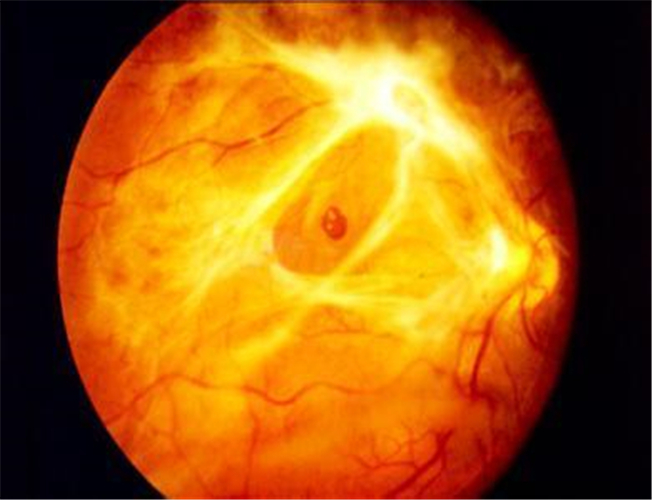

嚴重視網膜脫落

嚴重的視網膜脫落

血管膜視網膜脫落